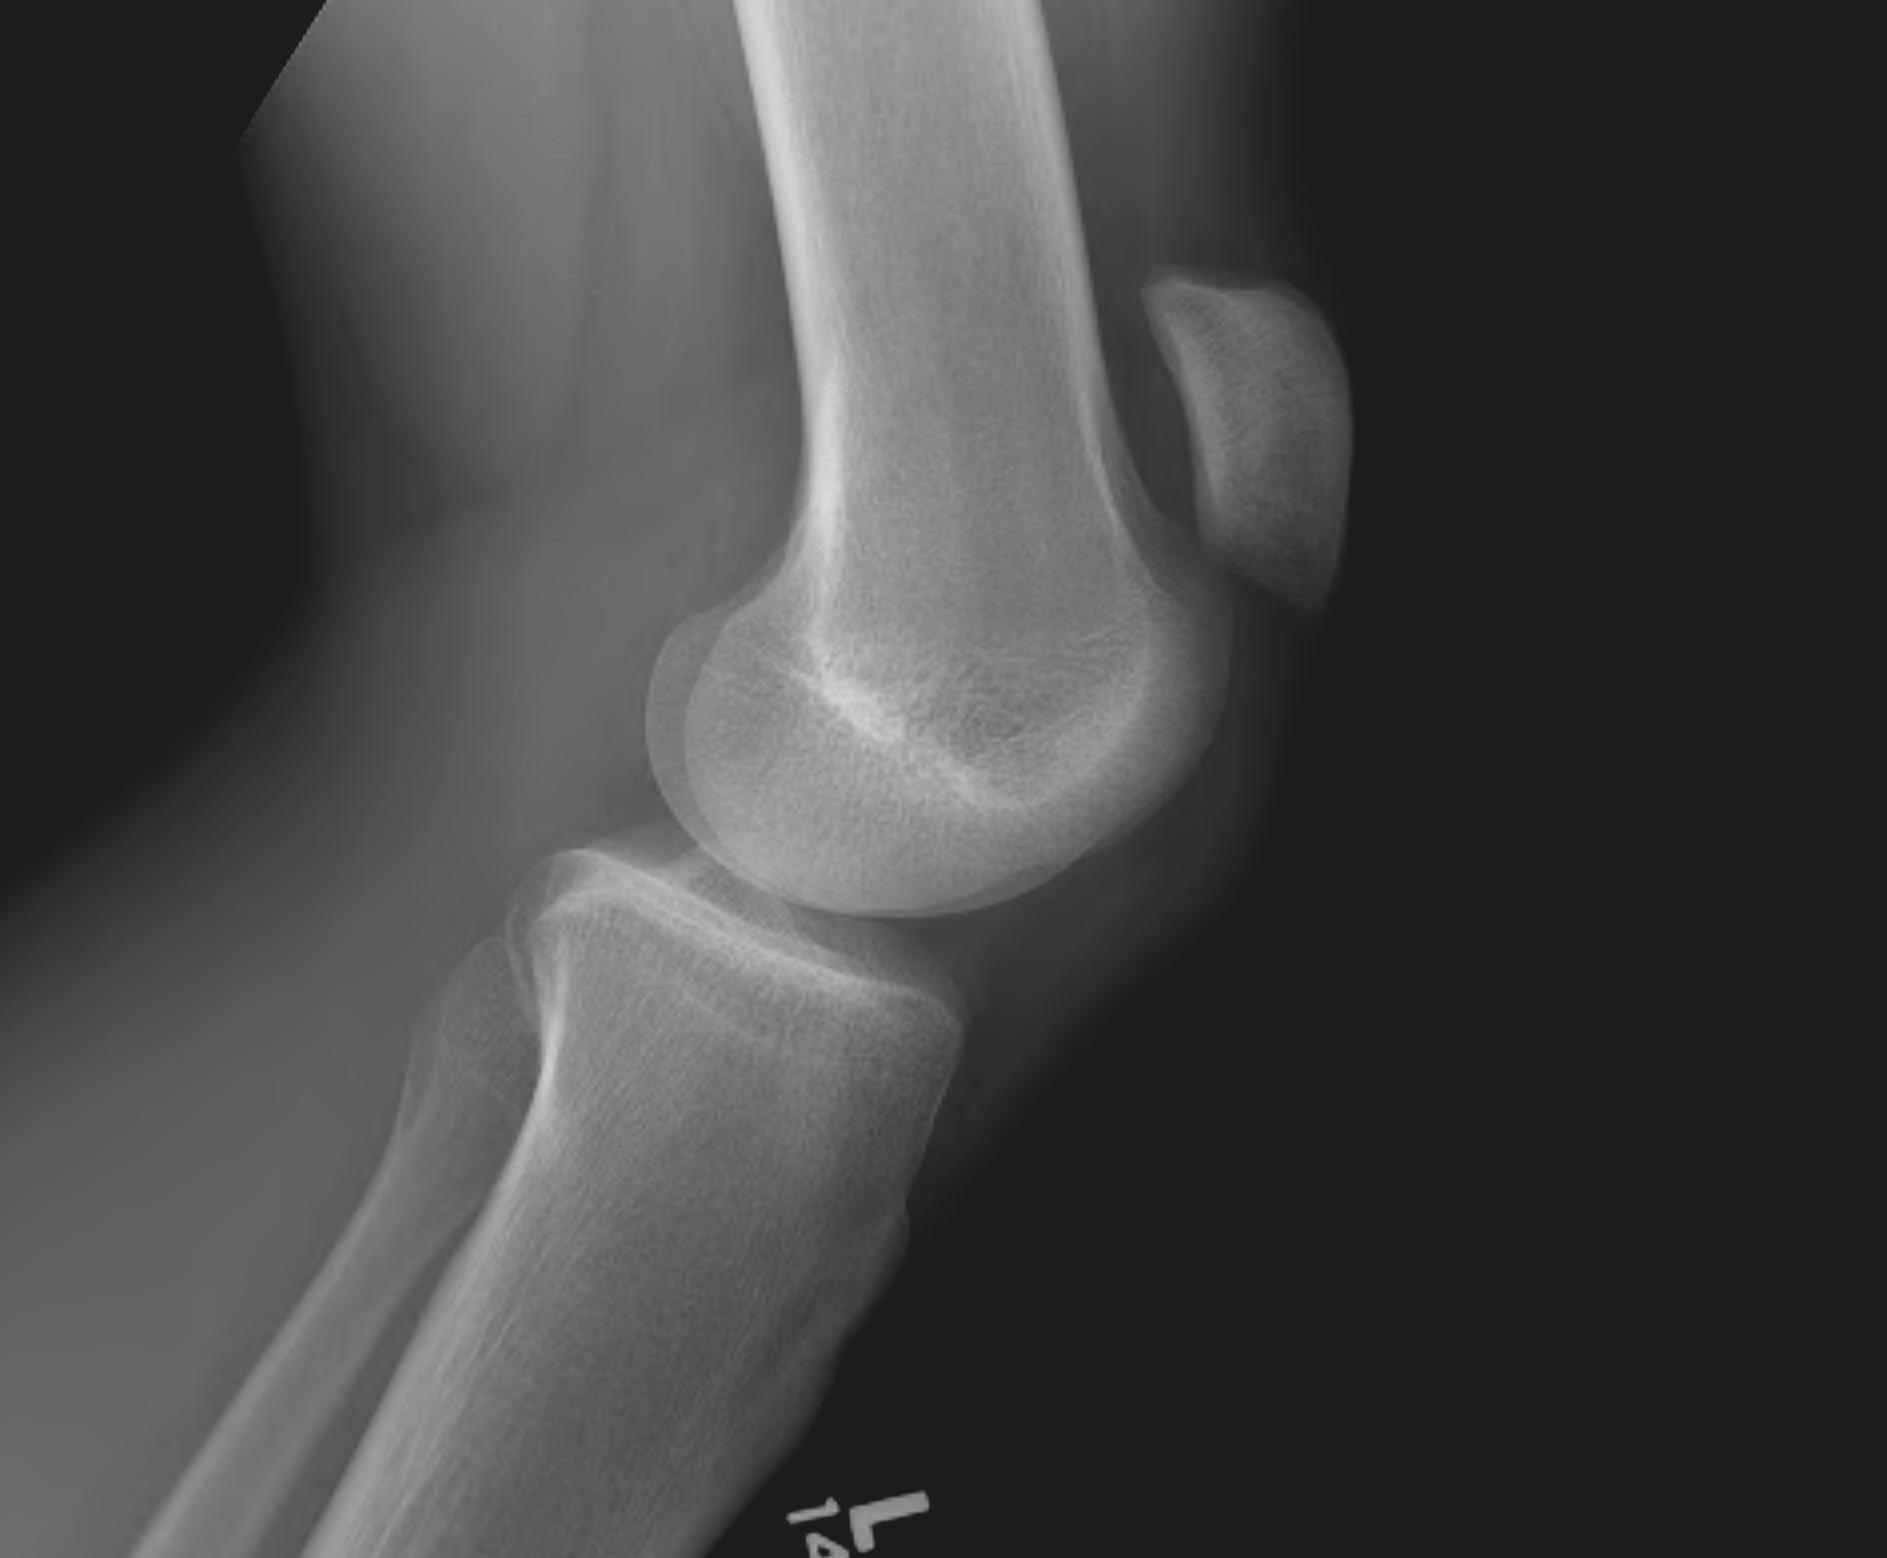

Xray

Patella alta / high riding patella

Distal Pole Patella Fracture